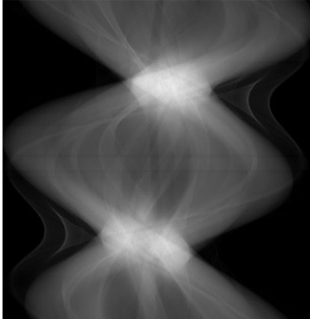

Low-Dose Computed Tomography (LDCT) technique, which reduces the radiation harm to human bodies, is now attracting increasing interest in the medical imaging field. As the image quality is degraded by low dose radiation, LDCT exams require specialized reconstruction methods or denoising algorithms. However, most of the recent effective methods overlook the inner-structure of the original projection data (sinogram) which limits their denoising ability. The inner-structure of the sinogram represents special characteristics of the data in the sinogram domain. By maintaining this structure while denoising, the noise can be obviously restrained. Therefore, we propose an LDCT denoising network namely Sinogram Inner-Structure Transformer (SIST) to reduce the noise by utilizing the inner-structure in the sinogram domain. Specifically, we study the CT imaging mechanism and statistical characteristics of sinogram to design the sinogram inner-structure loss including the global and local inner-structure for restoring high-quality CT images. Besides, we propose a sinogram transformer module to better extract sinogram features. The transformer architecture using a self-attention mechanism can exploit interrelations between projections of different view angles, which achieves an outstanding performance in sinogram denoising. Furthermore, in order to improve the performance in the image domain, we propose the image reconstruction module to complementarily denoise both in the sinogram and image domain.